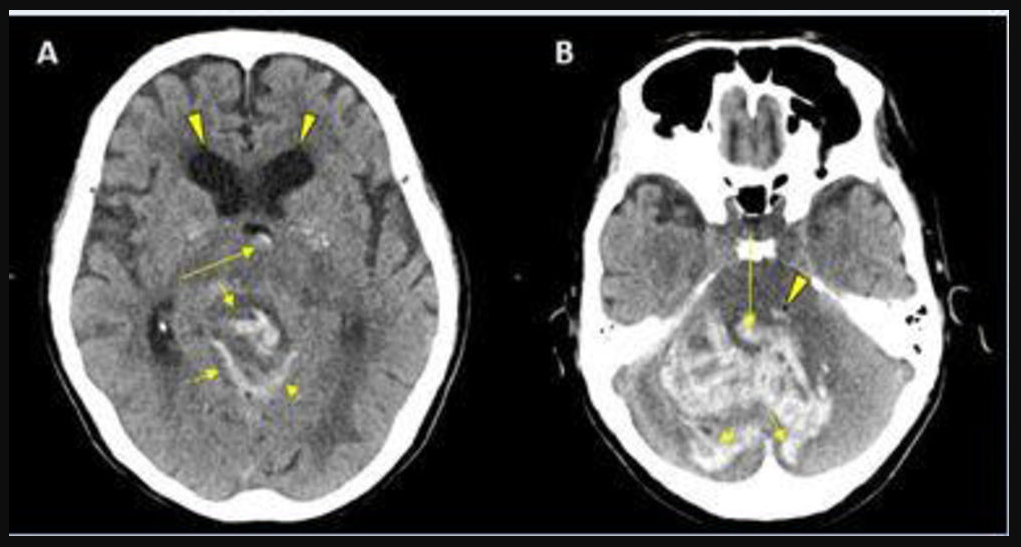

This photo gallery shows the variety of radiological presentations of COVID-19 (SARS-CoV-2) in medical imaging, including computed tomography (CT), radiograph X-rays, ultrasound, echocardiograms and magnetic resonance imaging (MRI). The radiology images show examples of typical COVID pneumonia in the lungs and the numerous complications the virus causes in the body in multiple organs, including the brain, kidneys, heart, abdomen and vascular system.